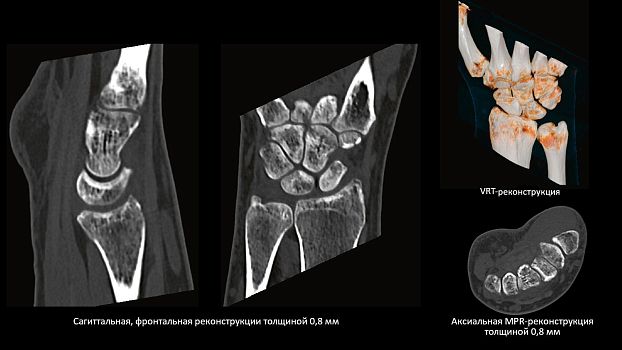

SOMATOM go.Up позволяет расширять клинический диапазон и развиваться, достигая существенных результатов. Благодаря использованию высоких технологий система обеспечивает результаты, которые ранее были доступны только на томографах высокого класса. Кроме того, SOMATOM go.Up хорошо подходит для целей лучевой терапии. Благодаря пакету RT Image Suite, установленном на рабочей станции сбора данных, можно без труда выполнять разметку, оценивать изображения и проводить оконтуривание мишеней для лучевой терапии.

Позволяет выполнять сканирование с низкой лучевой нагрузкой, что очень важно для оптимальной заботы о пациенте. SOMATOM go.Up выполняет сканирование больших диапазонов за одну задержку дыхания с высоким пространственным разрешением.

SOMATOM go.Up позволяет проводить скрининговые исследования лёгких и толстой кишки, а также исследования сердца для оценки коронарного кальция. Благодаря субмиллиметровой коллимации SOMATOM go.Up обеспечивает высокое пространственное разрешение, тем самым повышая чувствительность диагностики в онкологии.